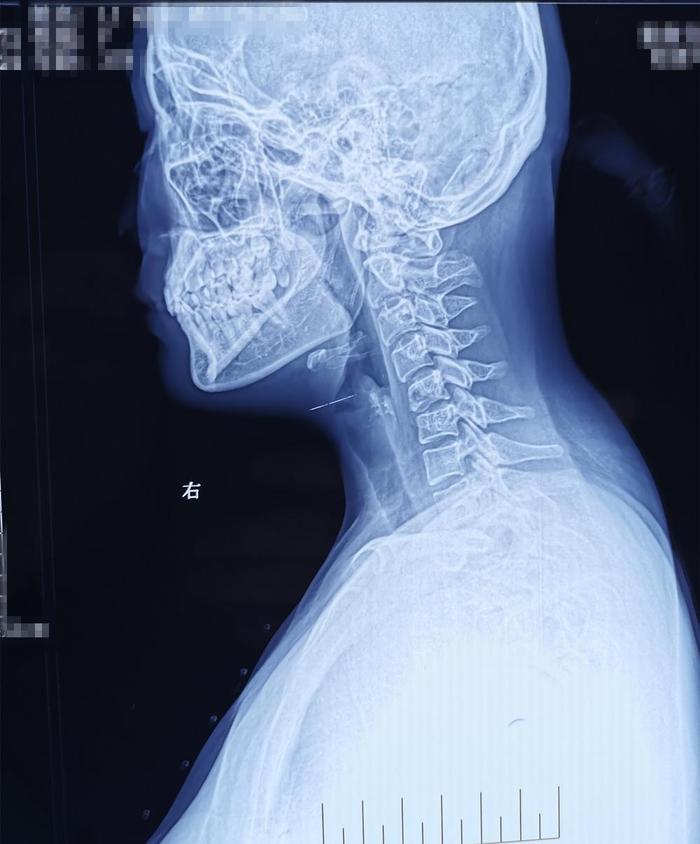

术后影像学资料: